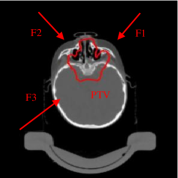

One common indication for proton therapy centers is represented by tumours extending both in the head and neck. As the tumour extends over a relatively big area, the treatment can result rather toxic for many organs at risk. These cases are usually treated with four fields, as shown in Fig.5: two coming from the front, aimed at covering the target volume at the level of the shoulders, two coming from behind, supposed to deliver the dose in the head part of the tumour. The drawback of this geometry is that, despite the dose constraints, the front fields irradiate OARs inside the head and, in the same way, the back fields release high dose to the shoulders, without being crucial for target coverage in that point.

Figure 5: Fields crossing the nasal cavities: axial CT slices with the green contour of the CTV and red contours of some OARs; the four fields F1, F2, F3, F4 are also indicated.